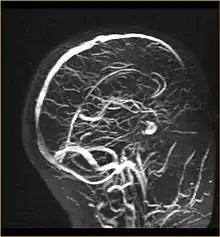

Ангіогра́фія (грец. αγγειον — судина і γραφω — пишу) — метод спеціального рентгенологічного дослідження кровоносних судин різних органів шляхом введення в артеріальну чи венозну систему речовин, які дають різку тінь в рентгенівських знімках. Ангіографія без контрастної речовини також можлива за допомогою МРТ.

- Магнітно-резонансна ангіографія (MRA)